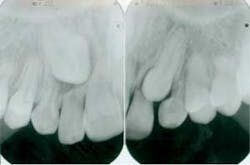

Before you begin treatment, take records. These include photos, x-rays, and diagnostic models. It is important to document the state of the patient prior to treatment. Regarding root resorption, it is essential to take radiographs. Any orthodontic treatment should include pretreatment and post-treatment radiographs that allow visualization of the roots. I recommend panoramic radiographs for this purpose. While it is common in general dentistry to take panoramic x-rays every five years, this is too long for patients in orthodontic treatment. Root resorption can be evident radiographically in as little as six months of orthodontic treatment. Because of this, I take panoramic x-rays every six to eight months in my practice.